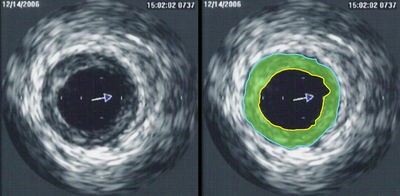

Ultrasonografia intravasculară (IVUS)

Reprezintă o investigație imagistică ce presupune explorarea spațiului vascular intracoronarian prin introducerea unei sonde la nivel arterial, care emite ultrasunete și captează reflexia țesuturilor.

Linia galbenă –lumenul vascular;

Linia albastră – membrana externă elastică;

Zona verde – placa aterosclerotică.